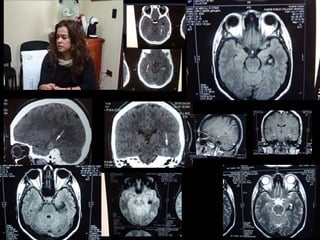

• TC permite mostrar la presencia de una

• Evidencia el tamaño, localización, edema

satelite, desplazamientos por efecto de

masa, invasión ventricular y la

hidrocefalia.

• Permite orientar el tratamiento y estimar

un pronóstico

DIAGNÓSTICO

• Algunos pacientes pueden presentar un

refuerzo periférico de la lesión al término

de la segunda semana, más frecuente en

hemorragias lobares y se puede confundir

con gliomas, metástasis o abscesos.

• RMN no ha significado una contribución

importante en el dx de ECV hemorrágico.